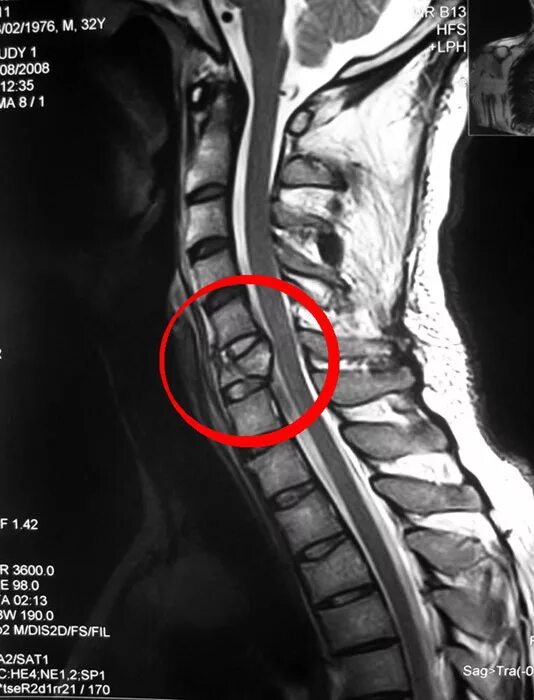

Мрт шейно поясничного отдела